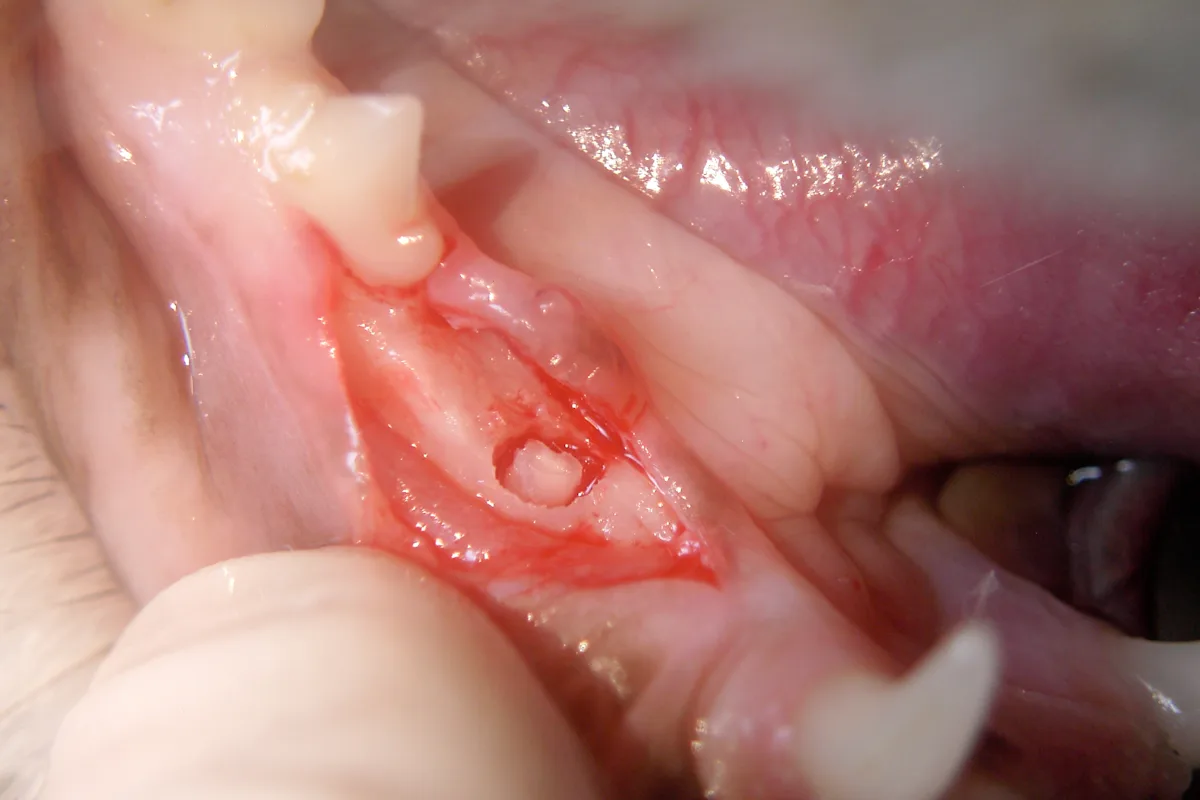

Step 4

The crestal alveolar bone is inspected for clinical evidence of root structure. The mesial root can be seen. The distal root is not evident.

Step 5

A taper diamond burr is used to smooth the crestal bone and reevaluate for any clinical evidence of root structure. Retraction of the lip or gingival margins may be necessary while performing this osteoplasty.